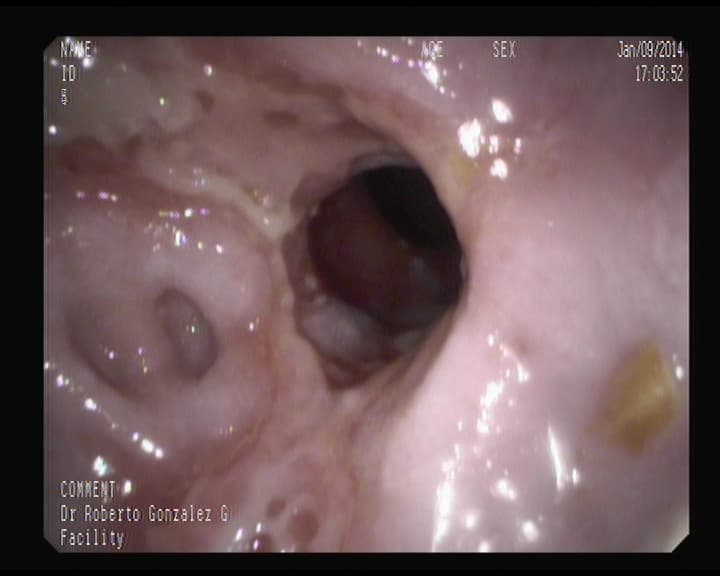

Otra cara de un orificio apendicular normal

Orificio apendicular visto desde el intestino grueso, sin signos inflamatorios.

Visión del orificio apendicular en ciego.

Ese orificio oscuro, es la entrada del apéndice.